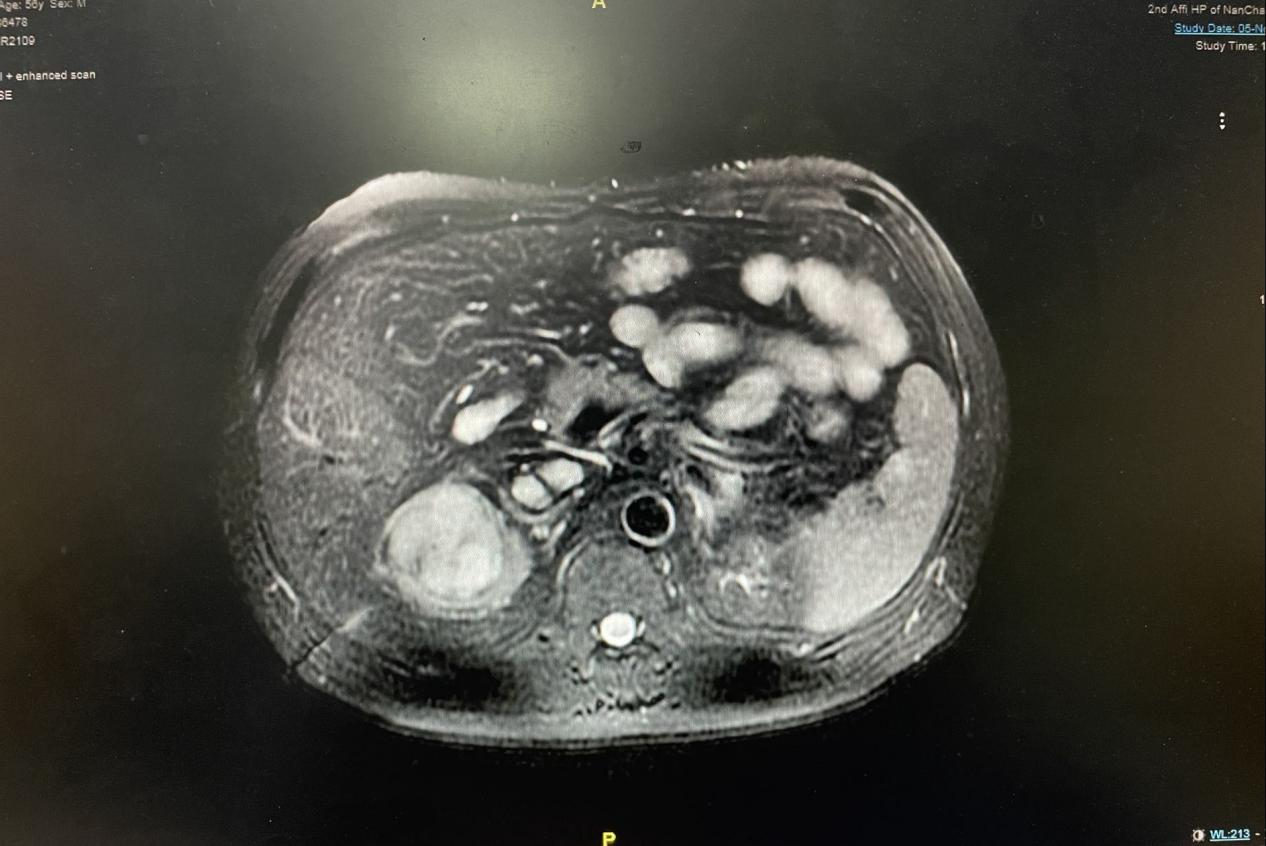

患者为中年男性,因彩超检查发现右肾肿瘤入院。完善检查发现右肾癌并右肾静脉、腔静脉癌栓,下腔静脉癌栓位置高于肝尾状叶,癌栓长度接近 6 cm, 属于 II 级癌栓。明确诊断后,刘飞教授团队决定行肾癌根治性切除并腔静脉癌栓取出术。该手术是泌尿外科最具挑战性的手术,手术难度和风险极大,术中可能存在癌栓脱落引起致命性肺栓塞和大出血的风险。